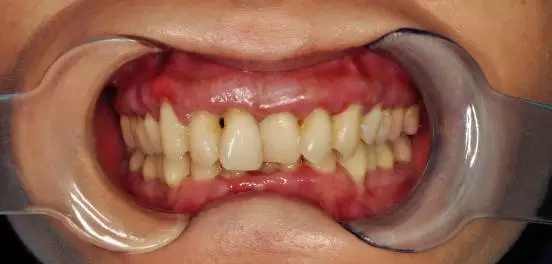

陸小姐,35歲,患者數(shù)月前發(fā)現(xiàn)下前牙松動,進食時疼痛,刷牙出血;

檢查:全口口腔衛(wèi)生差,牙結(jié)石嚴重,牙齦紅腫,探之出血牙齒三度松動,前牙牙根暴露,X片顯示牙槽骨吸收嚴重

診斷:牙周炎(重度)

牙齦出血有好轉(zhuǎn),但患牙仍有松動,能夠發(fā)現(xiàn),齦乳頭萎縮,醫(yī)生繼續(xù)采用階段性牙周治療,慢慢讓牙齦紅腫消除,繼續(xù)常規(guī)消毒,齦下刮治,沖洗,上藥?;颊咝枰龊萌粘5目谇蛔o理。

檢查:牙齒松動度緩解,牙齦邊緣無紅腫,無明顯探診出血